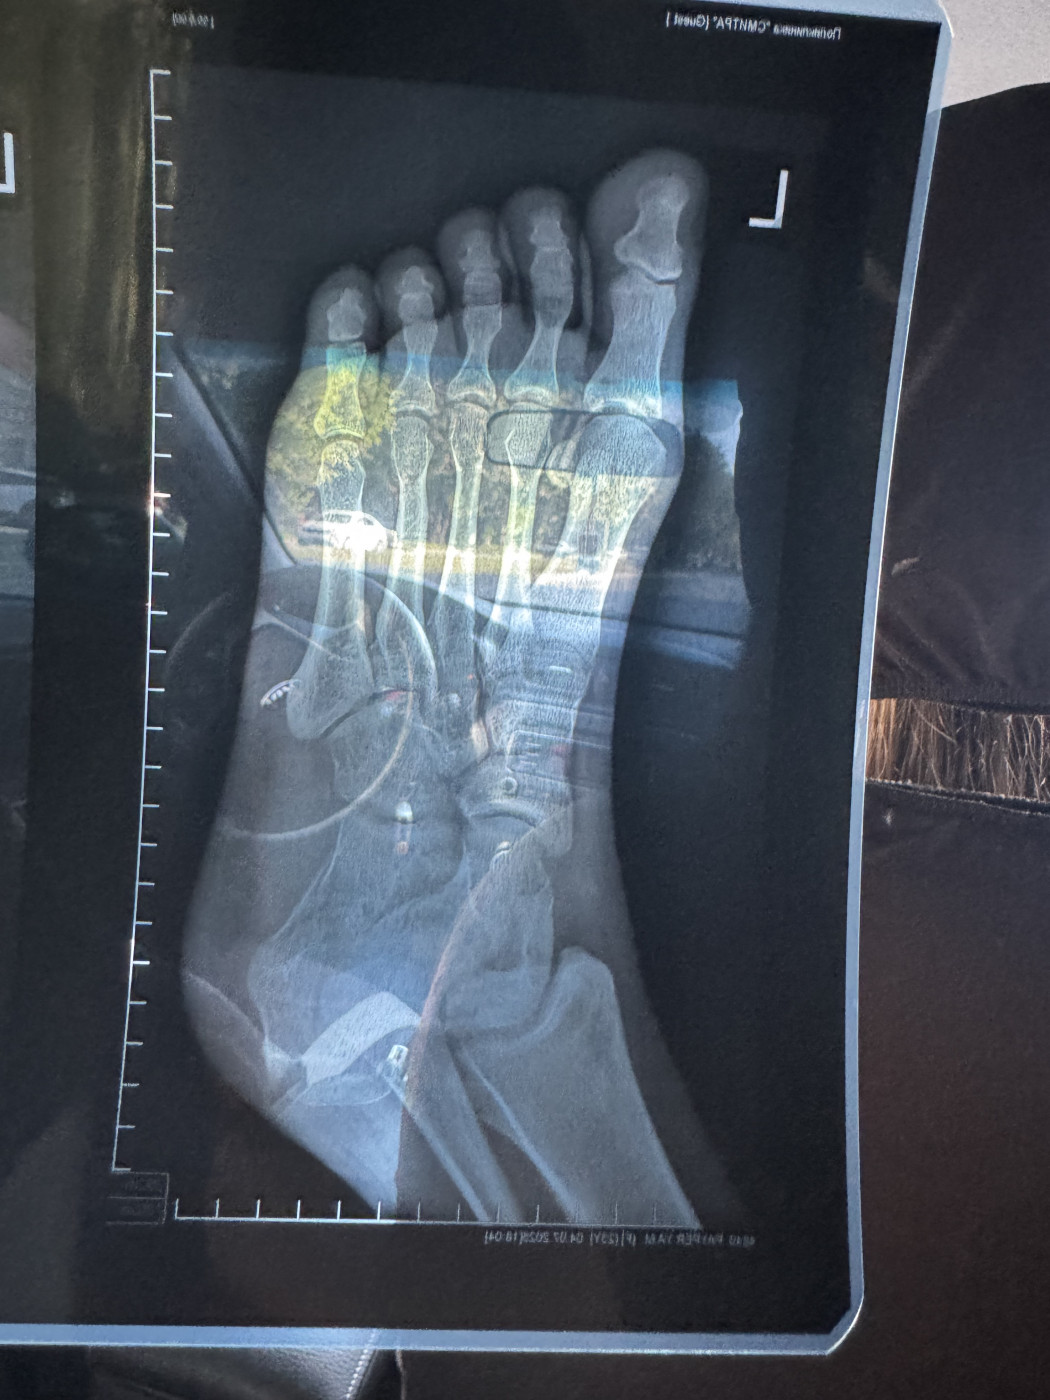

Перелом пяточной кости   2 ответа

Здравствуйте, через 30 дней после перелома сделали рентген снимок, который оказался намного детальней первого, я на нем увидел странность, а врач не дает четкого ответа, прикладываю снимок, посмотрите пожалуйста, нет ли второго перелома в правой части кости, сейчас врач сказал ходить в лангете еще 14 дней, после этого снять САМОМУ, без приема, и начать реабилитацию, пытаться наступить на ногу к 60 дню от перелома